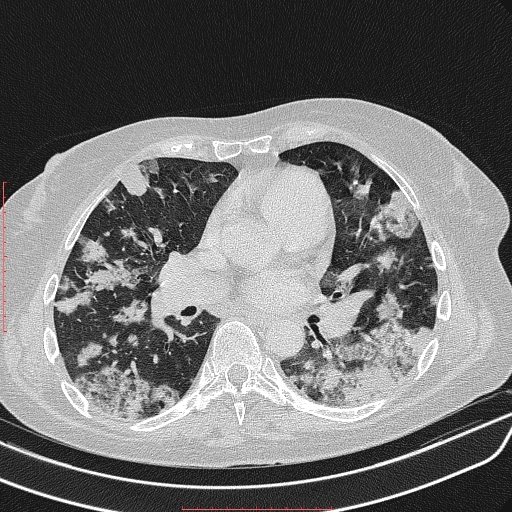

Аденокарцинома 4 стадия

Аденокарцинома 4 стадия 115 фото